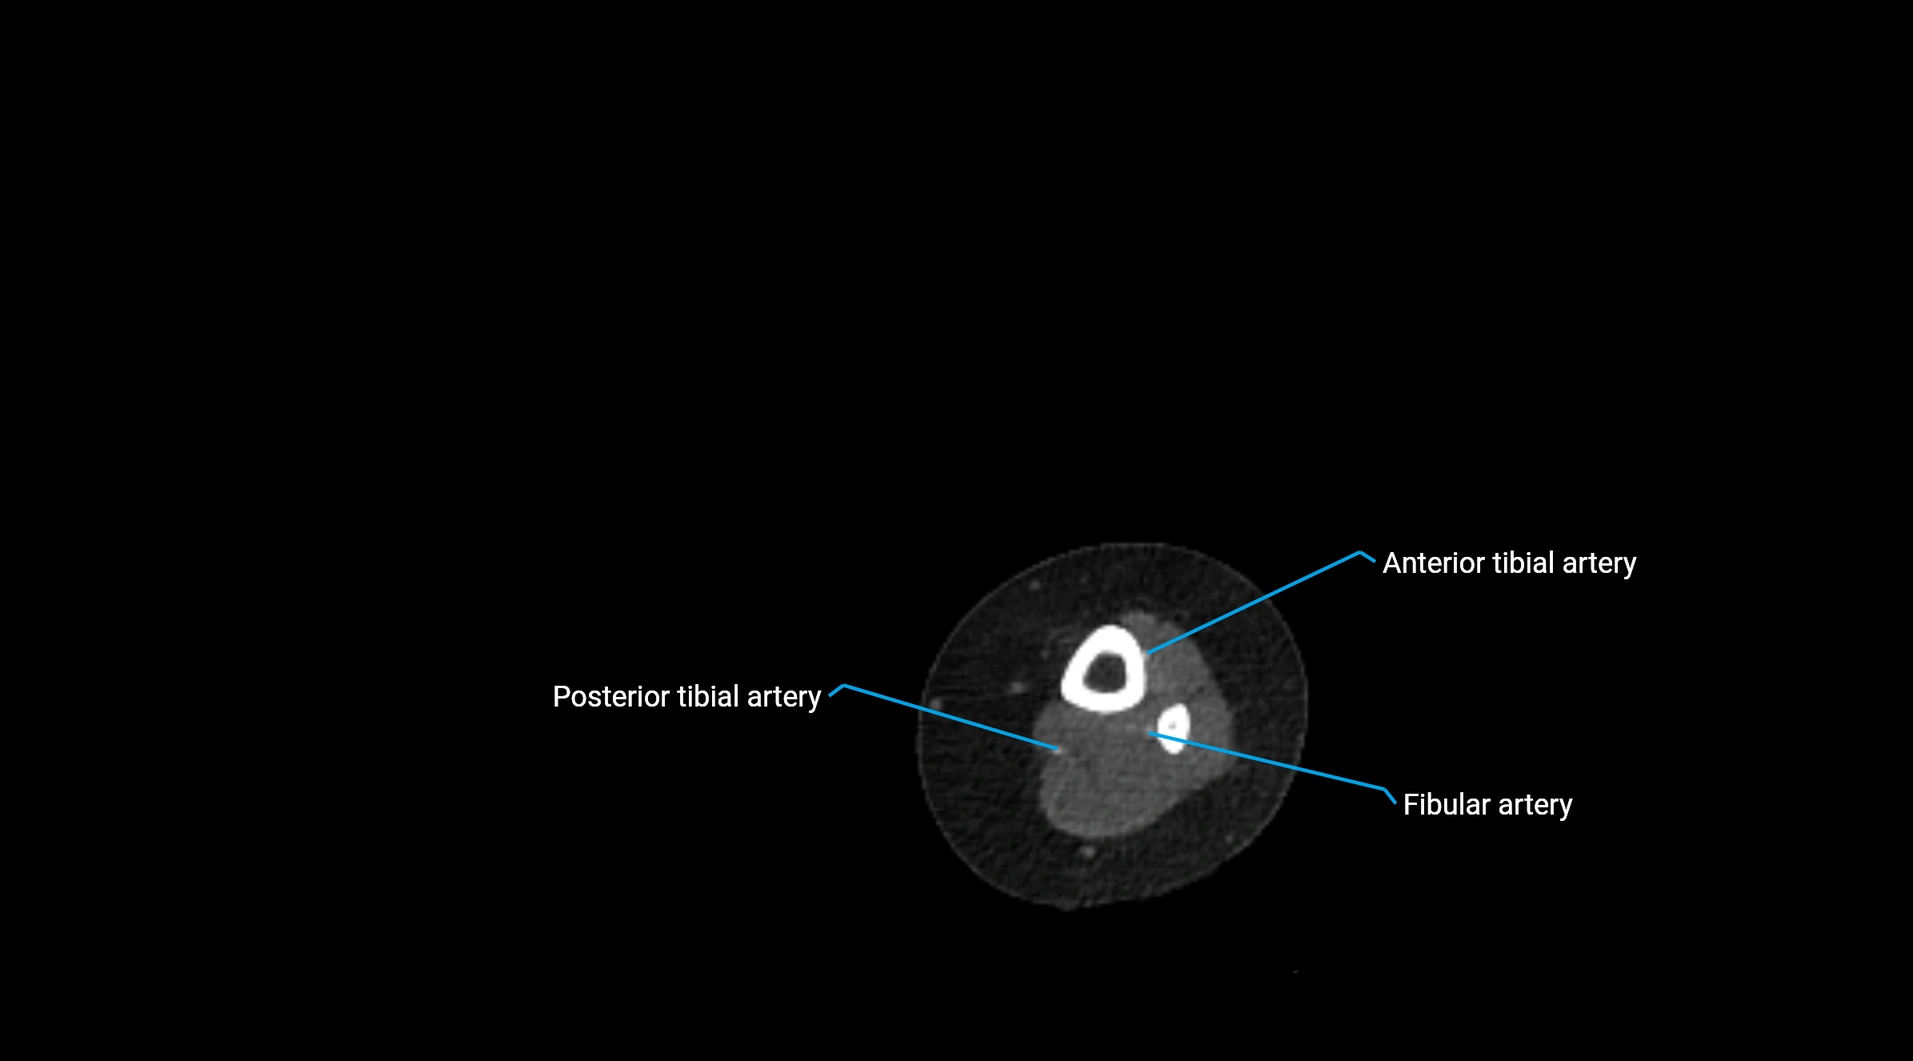

CT Appearance

Non-contrast CT:

• Appears as a tubular soft tissue structure anterior to vertebral bodies

• Calcified atherosclerotic plaques appear as hyperdense foci along the wall

• Useful for screening abdominal aortic aneurysm (AAA) size and mural calcification

Contrast-enhanced CT (CTA):

• Gold standard for abdominal aortic imaging

• Provides excellent detail of lumen, wall, aneurysm, thrombus, and branch vessels

• Multiplanar and 3D reconstructions help in aneurysm measurement, stent graft planning, and dissection evaluation

• Detects acute rupture, traumatic injury, or occlusion with high sensitivity